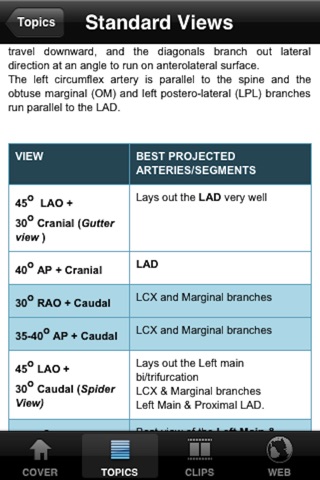

CathLab App provides easy to access information for education in the setting of cardiac catheterization laboratory. The information elements include description of different procedural basics as well as illustrations. In addition video clips inside the app and from world wide web supplement the content in a meaningful way.